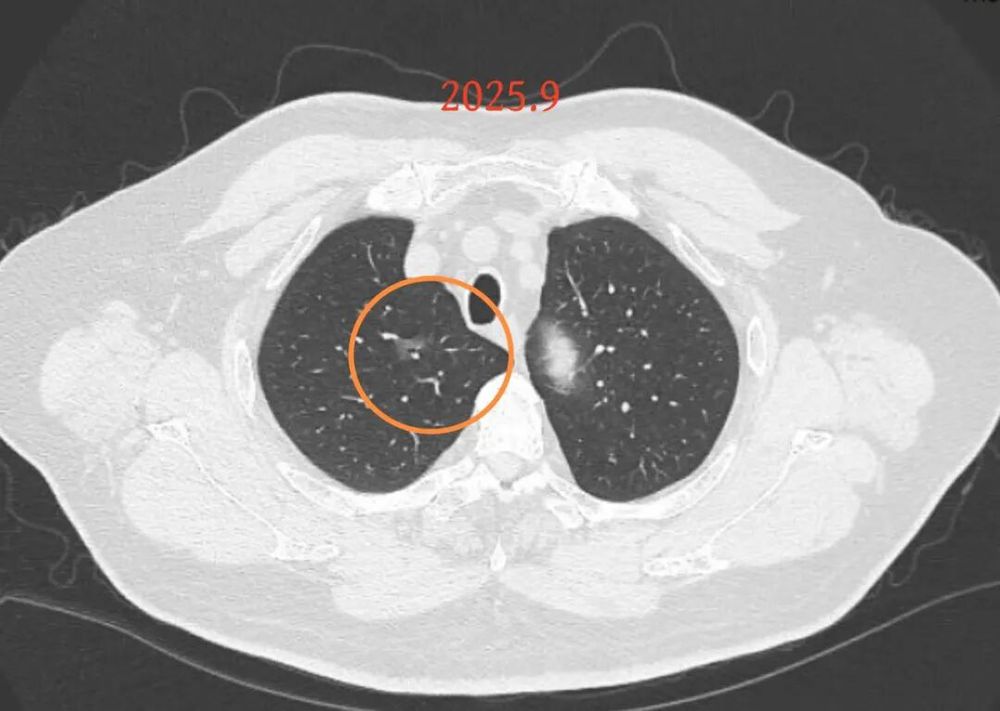

第二次问诊:2025.9

影像展示与分析:

病灶B似乎灶内有少许密度略偏高,但瘤肺边界欠清晰,总体说不上太显著的进展。

我的意见:

右肺上有两处病灶,仍然是磨玻璃密度,整体轮廓较为清楚,对比23年的说不上非常明显的进展。确实需要考虑微浸润性腺癌可能性大(上次我也说原位癌或者微浸润性腺癌)。主要纠结于位置太靠中间,如果手术基本上得切除右肺上叶。我的想法是已经75岁的年纪,如果进展很慢的话,是不是也不是一定得开刀。或者随访看它进展情况,到时候再来考虑。个人稍微倾向于仍然六到九个月复查,有进展并风险增加再手术,或者其他方法干预。意见供参考!

后续交流:

当时结友自己还觉得有点实性成分,血管感觉也有增粗。而我觉得整体密度仍是磨玻璃,轻微的变化仍不足以影响临床决策的程度。